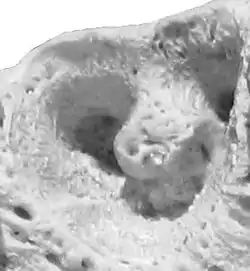

![]() Alveola of the second premolar tooth in a bovine maxillary bone | |

Dental alveoli (singular alveolus) are sockets in the jaws in which the roots of teeth are held in the alveolar process with the periodontal ligament. The lay term for dental alveoli is tooth sockets. A joint that connects the roots of the teeth and the alveolus is called gomphosis (plural gomphoses). Alveolar bone is the bone that surrounds the roots of the teeth forming bone sockets.